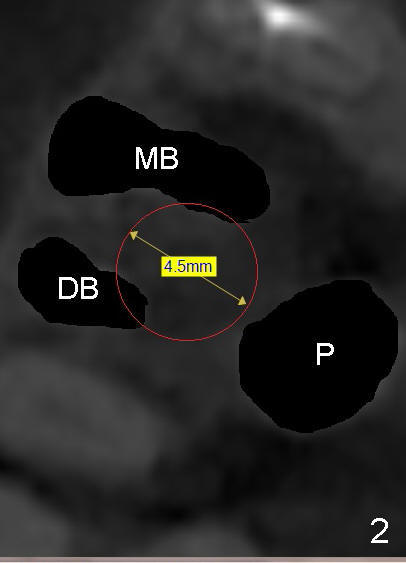

A 51-year-old man requests taking care of hemorrhage and odor associated with the tooth #3 (Fig.1). Due to religious and financial issues, the neighboring teeth will be treated later (supraeruption of #2 (arrow) and periapical radiolucency of #4 (*)). CBCT reveals that the septum of #3 is large enough to hold 4.5 mm implant (Fig.2). In fact osteotomy is created as planned in the septum using drills and taps (Fig.3 after removing 4.5x20 mm tap). Primary stability is obtained with a 4.5x20 mm implant (> 60 Ncm, Fig.4). The gap (*) is bone grafted; an abutment is placed (Fig.5 A); an immediate provisional is fabricated and cemented to cover the socket (Fig.6 P). When the socket heals in 3 weeks postop, the provisional and the abutment are removed for easy oral hygiene. Bone regenerates around the implant 3.5 months postop (Fig.7 *), but the 2nd molar has shifted mesially (arrow), presenting a restoration challenge.

It appears that the upper molar shifting is quite common (6 7), probably due to less dense bone in the maxilla. It is the best to fabricate and keep an immediate provisional to hold the mesiodistal dimension and ask the patient to improve local oral hygiene during osteointegration. The implant crown is functioning 4 years 2 months post cementation while there is severe bone loss at #2 (Fig.8). An immediate implant could be placed at #2 (Fig.9), while a wide delayed implant will be placed at #31 (Fig.10).